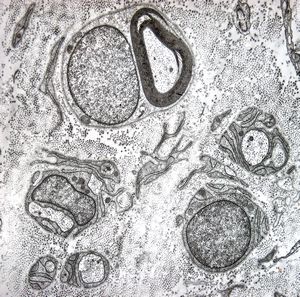

F,50y. | progressive multifocal leukoencephalopathy- viral particles in a glial cell

F,50y. | progressive multifocal leukoencephalopathy- viral particles in a glial cell

F,50y. | progressive multifocal leukoencephalopathy- viral particles in a glial cell